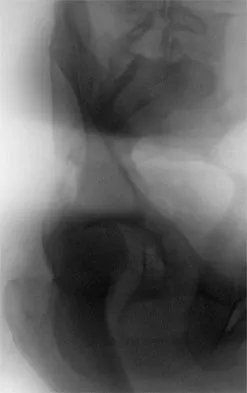

Figure 33a shows a line drawing of a normal hemipelvis. The anterior acetabular rim is bold. Figure 33b illustrates a hemipelvis with a crossover sign, which is indicative of what acetabular pathology?

In a normal AP pelvis radiograph, the anterior rim of the acetabulum runs medially and distally, diverging from the posterior rim which runs much more vertically. In excessive acetabular retroversion, the anterior rim (bold line in Figure 33b) and posterior rim start laterally, and as these lines progress medially and distally, the anterior line crosses the posterior line. This predisposes to femoral acetabular impingement. Reynolds D, Lucas J, Klaue K: Retroversion of the acetabulum: A cause of hip pain. J Bone Joint Surg Br 1999;81:281-288.

- Espinosa N, Rothenfluh DA, Beck M, et al: Treatment of femoro-acetabular impingement: Preliminary results of labral refixation. J Bone Joint Surg Am 2006;88:925-935.